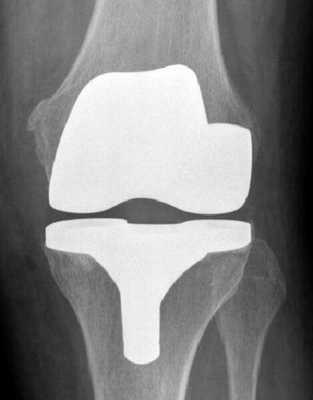

Самый распространенный тип импланта коленного сустава.

Рентген после операции. Протез стоит корректно.